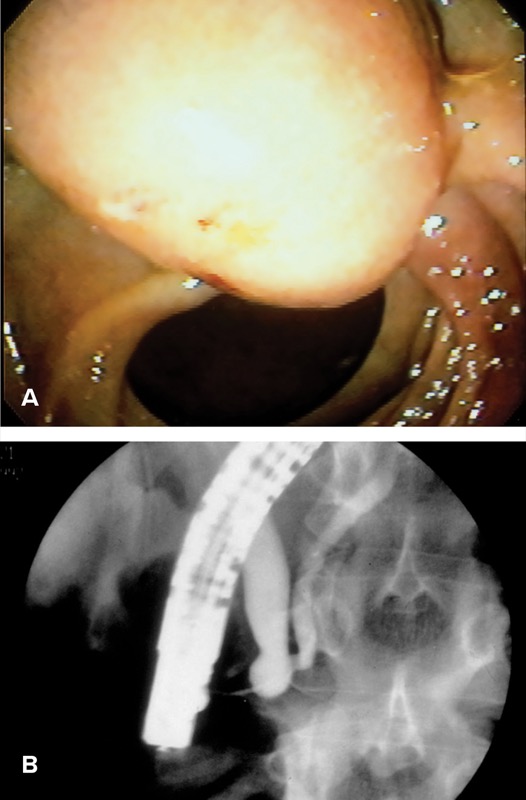

Congenital pancreaticobiliary malformations, often incidentally found on MRI/MRCP, can lead to RAP. Choledochal cysts are cystic dilations of the intrahepatic or extrahepatic biliary tree and may be single or multiple. Todani type III choledochal cysts, or choledochoceles, are cystic lesions that arise from the intramural bile duct or intra-ampullary common channel (Figure 5A, 5B).83 In type A choledochoceles, as originally defined by Sarris and Tsang,84 the intramural bile duct communicates with a cystically dilated segment, which then drains into the duodenal lumen via the separate papillary orifice.85,86 In type B choledochoceles, the bile duct drains normally into the duodenum, with the choledochocele arising as a diverticulum from the intra-ampullary common channel.44,87

During ERCP, the papilla associated with the type A choledochocele may be recognized by its bulging intramural portion of the bile duct, but it is soft when probed with a catheter tip.88 Alternatively, the papilla may appear less prominent but progressively enlarges with contrast injection that fills the cyst. Type B choledochoceles often appear endoscopically as a pendulous duodenal mass, with the ampullary orifice immediately proximal to this mass.87

Choledochoceles commonly present with pancreatitis (38%-70%),44,89 but they are an uncommon overall cause of IAP due to their low prevalence.89 The most widely accepted mechanism of AP in patients with choledochoceles is obstruction of outflow with subsequent ductal hypertension, or bile reflux into the pancreatic duct.90

MRCP can detect choledochoceles with reasonable accuracy. In a study of 72 patients using ERCP as the gold standard, the sensitivity and specificity of MRCP in diagnosing type III choledochal cysts was 73% and 100%, respectively.91

EUS is also a viable diagnostic modality, but its utility in the diagnosis of choledochoceles is limited to case reports.92,93

While surgical therapy (either excision or sphincteroplasty) has been the historical approach to choledochoceles, endoscopic therapy with ERCP is considered to be a safe and effective alternative in most patients.87 Endoscopic management involves either unroofing the cyst, BES, snare resection, or a combination of the above, depending on cyst type and endoscopist preference. A review of published case reports suggests a resolution of AP episodes in 13 of 14 cases (93%) after endoscopic intervention.85,94-97 Anomalous pancreaticobiliary junction is rare, occurring in 0.2% of European populations, but is more prevalent in Asian populations and often is associated with choledochal cysts (40%-70%).44,98 Patients with anomalous pancreaticobiliary junction may experience AP through bile reflux into the pancreatic duct, and BES can be beneficial in preventing further AP episodes.